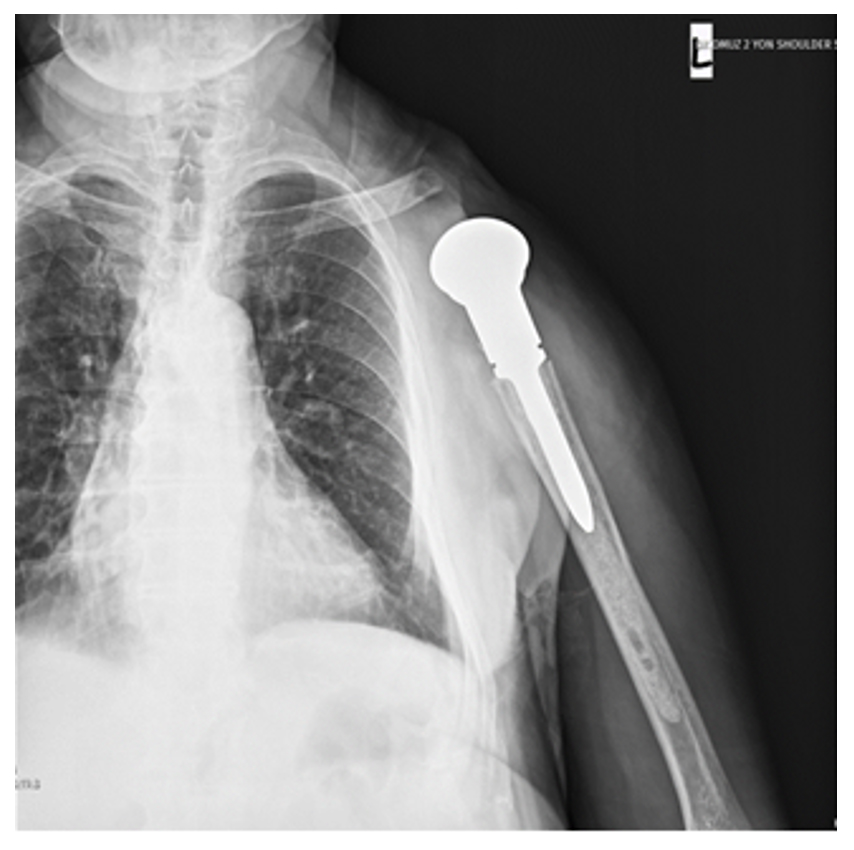

Ameliyat Sonrası: Röntgende rezeksiyon sonrası proksimal humerus tümör protezi ile yapılan rekonstrüksiyon.